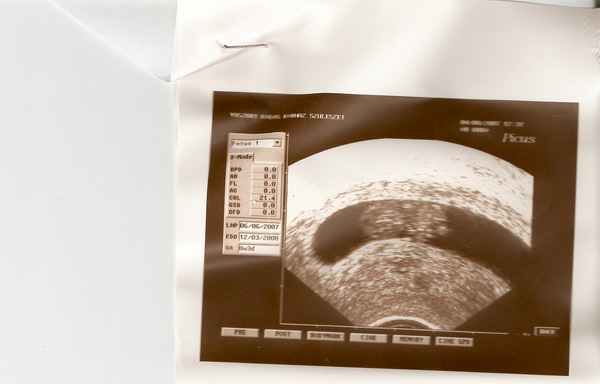

Szakadék: gratulálok! De jó neked, már várom én is a keddet, hogy halljam a szívhangot.